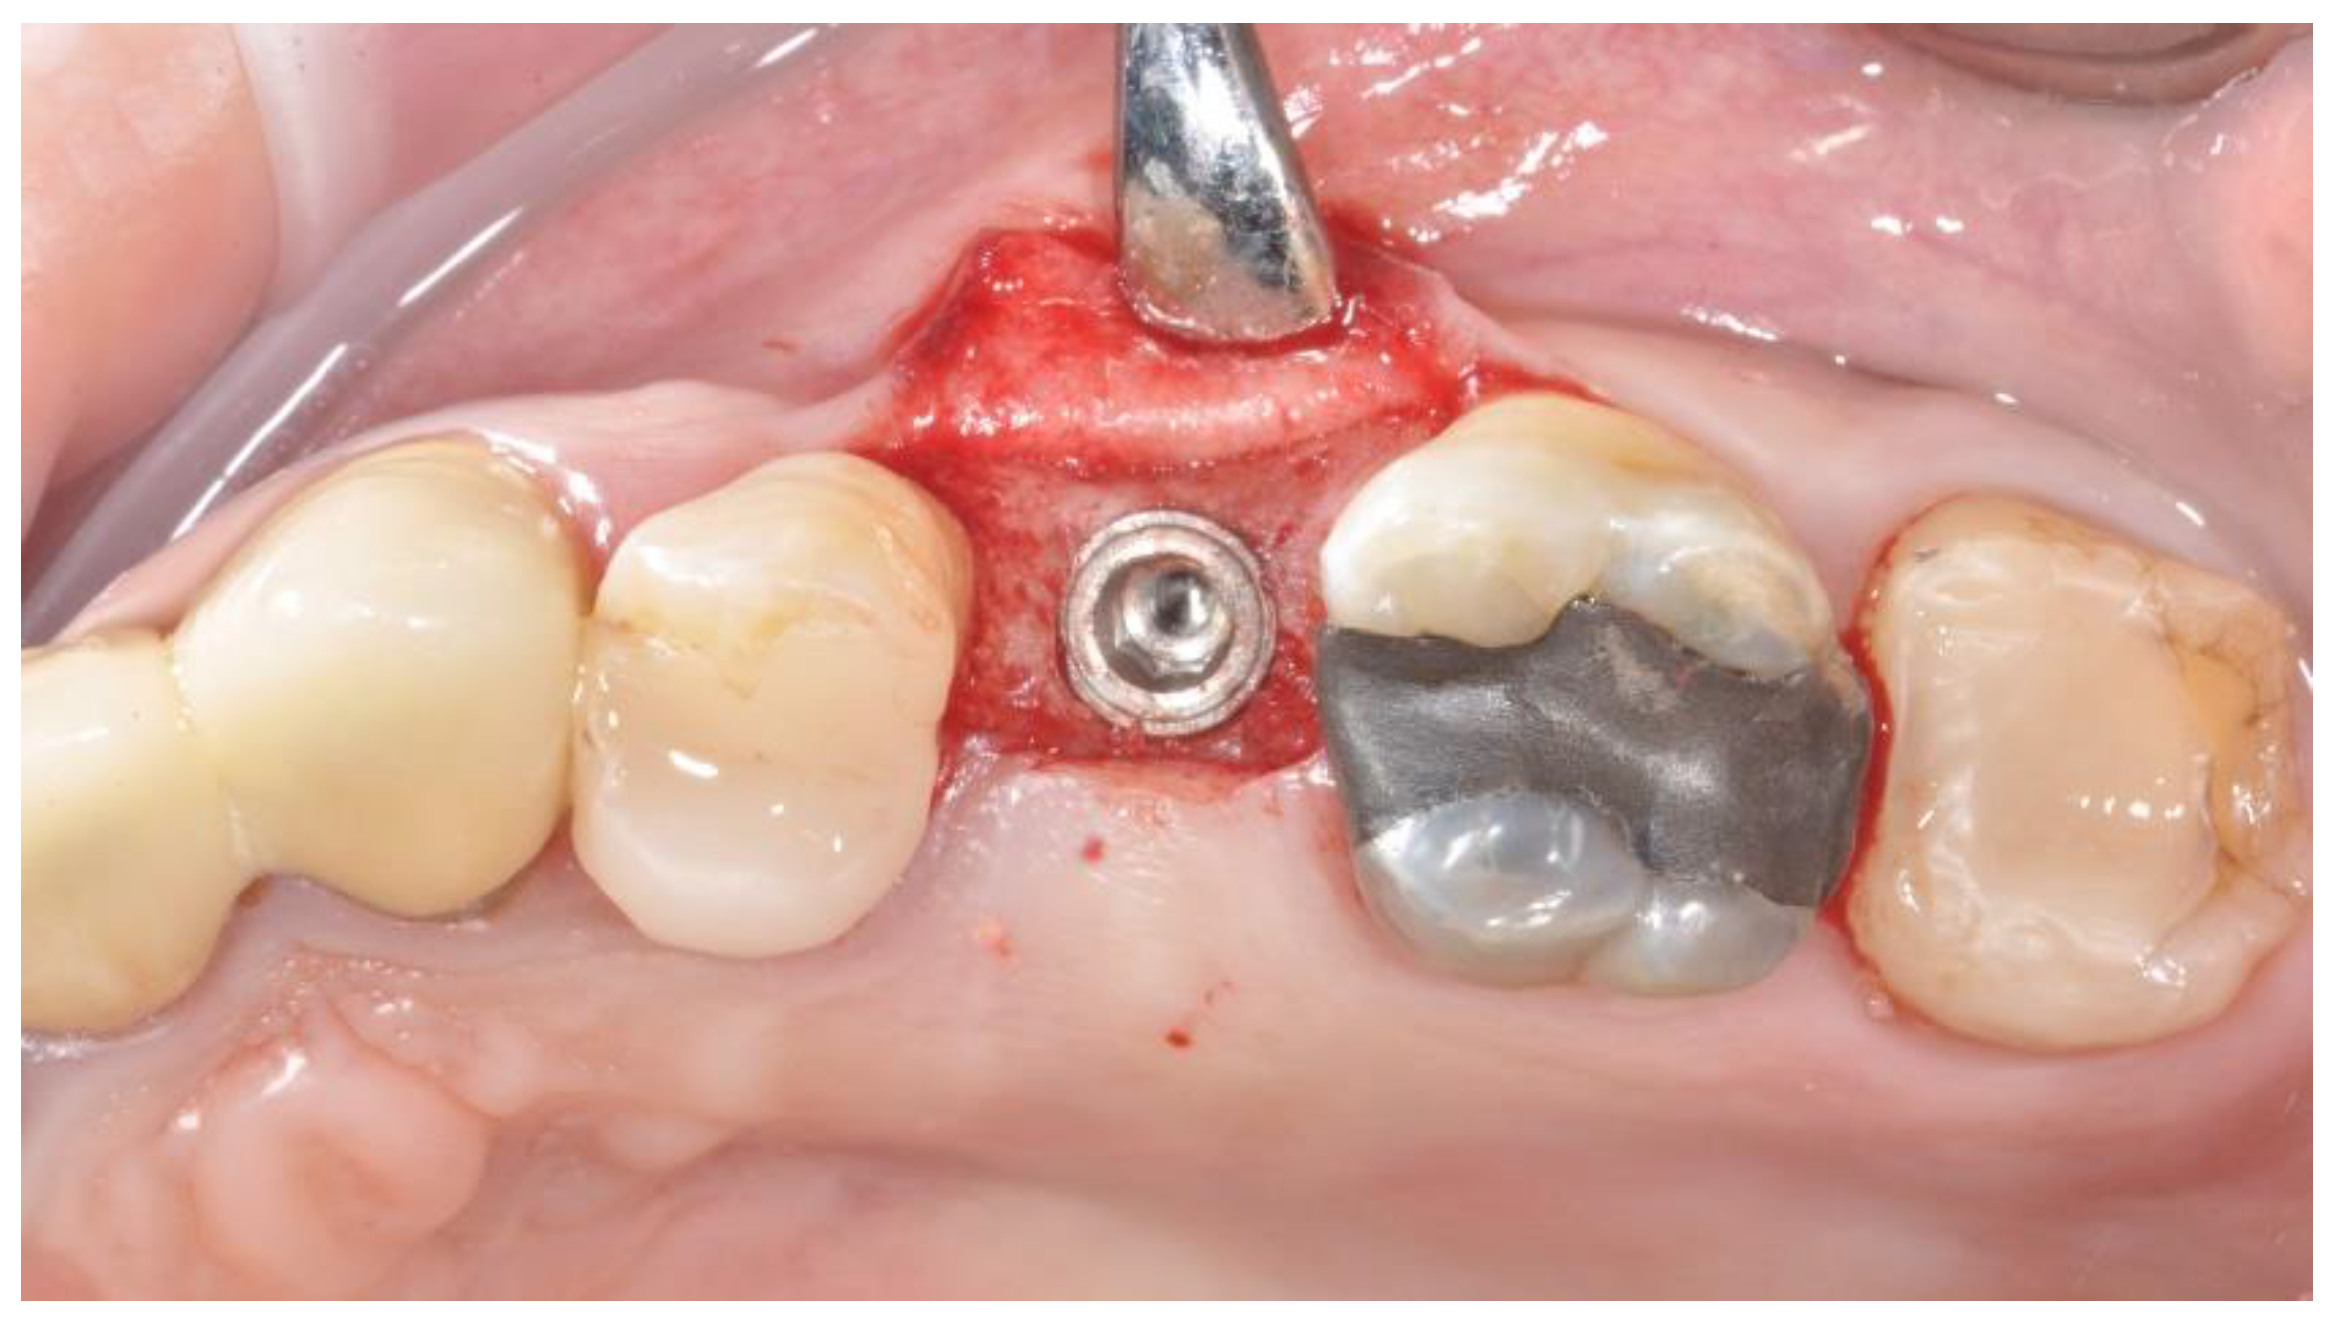

2.2. Surgical Procedures